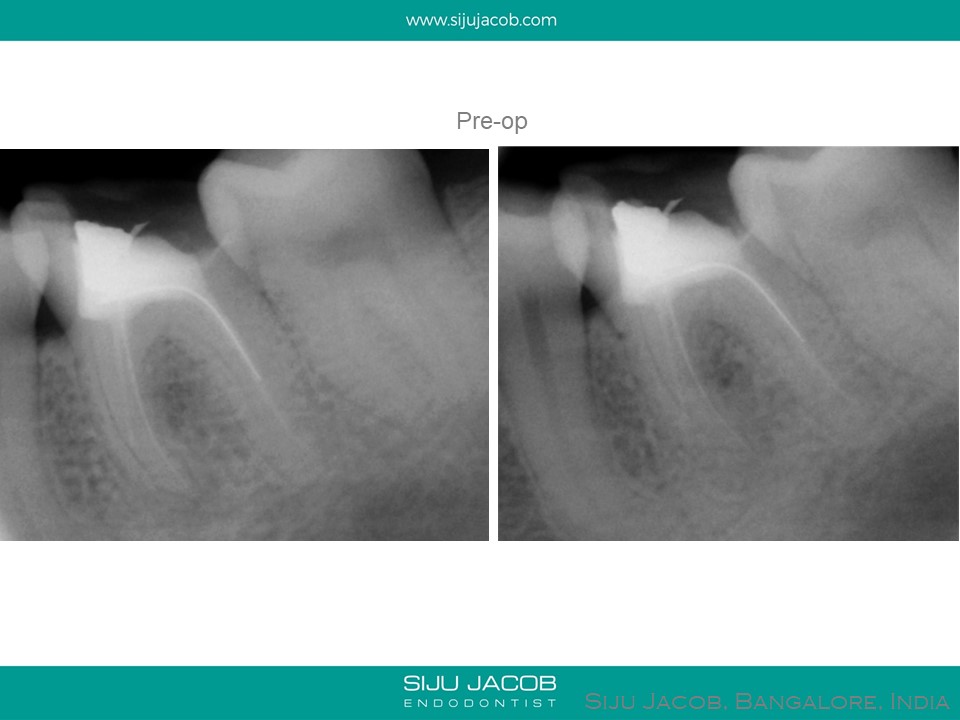

This is a case from 2006. Sometimes, when you look at these cases, we realize how much our treatment philosophies have changed over the years. This tooth was asymptomatic and the endo done several years ago. So, what benefit did me doing the re-endo have? Other than being a better “process centered outcome”, from a patient centered outcome, did it really matter? In fact, I probably made the prognosis worse by removing too much tooth structure. These days, when we get a case like this, we have a discussion with the patient before treating. Sometimes, we leave cases like these alone (No re-endo) and advise just a permanent restoration.